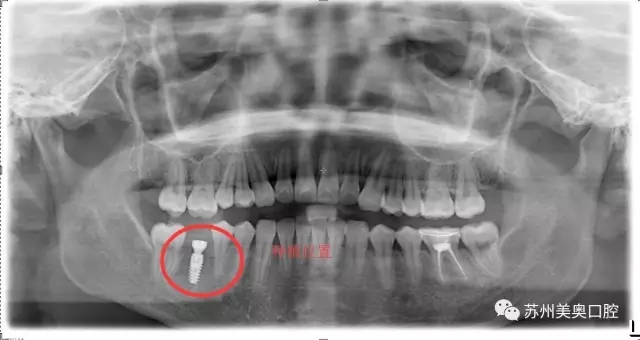

光学显微镜主要用于放大微小物体成为人的肉眼所能看到的仪器,所以被广泛应用于医学研究和临床手术中。口腔显微种植高精度可以精确到1毫米,将细微的口腔解剖结构放大近30倍,患者看到的下图仅仅放大了10倍。

相比于传统肉眼观察,显微口腔治疗为医生提供了聚焦光源和放大的清晰视野,明确分辨微小的神经血管,便于医生更换更小更精密的工具,进行的治疗,让种植牙更加安全高精。苏州美奥显微口腔治疗利用现代医疗科技一步一步实现着口腔治疗微观高精化。

“这颗牙齿的缺失,不仅增加了其他牙齿的咀嚼负担,缺牙边上的牙齿已经慢慢倾斜了。

我很久之前就想把牙齿种起来,只是担心牙槽骨那里已经很狭窄了,再加进一颗钉子会不会很不安全。直到看到美奥口腔的显微种植,术区可以放大到30倍,口腔视野很清晰,觉得种植很安全,所以才决定进行显微种植牙治疗。”